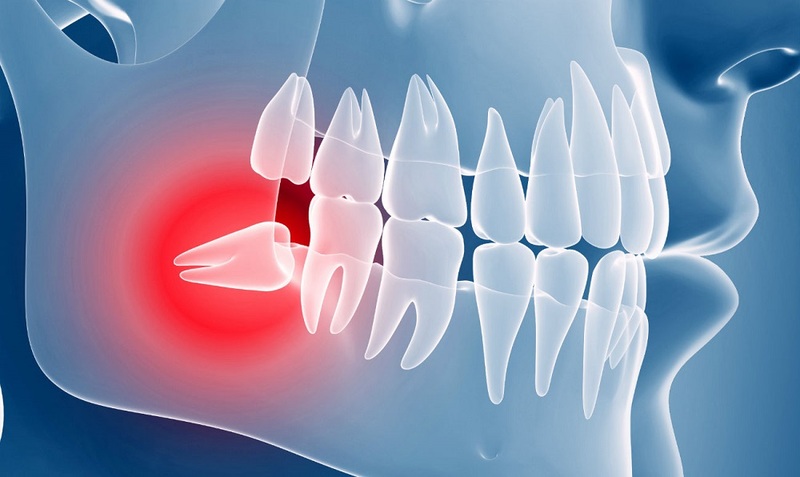

Что такое ретинированный и дистопированный зуб мудрости?

Ретинированный — непрорезавшийся зуб, он полностью скрыт под десной. Не до конца прорезавшийся зуб называют «полуретинированным». Опасность ретенции заключается в том, что при прорезывании моляра может развиться воспаление десны.

Дистопированный — аномально расположенный зуб. Он либо прорезался не на своём месте, либо развился под неправильным углом (наклонен в сторону), либо повёрнут вокруг своей оси. В стоматологической практике наблюдались аномалии, когда дистопированные зубы росли корнями вверх.

Зуб мудрости может расти как с одним из этих дефектов, так и сразу с двумя. Ретенция и дистопия, как правило, сопровождаются воспалением десны, отёком мягких тканей и другими малоприятными симптомами. Худший вариант развития событий — смещение зубного ряда и, как следствие, длительное и дорогостоящее лечение у ортодонта.

Если восьмёрка дистопирована, ретинирована или всё сразу, то быстро и просто избавиться от неё не получится. Для удаления проблемной восьмёрки врач может использовать скальпель, бормашину, лазер, элеватор и другие хирургические инструменты. Этапы операции:

- При необходимости высверливание или отсечение костной ткани, разделение зубного корня на несколько частей.